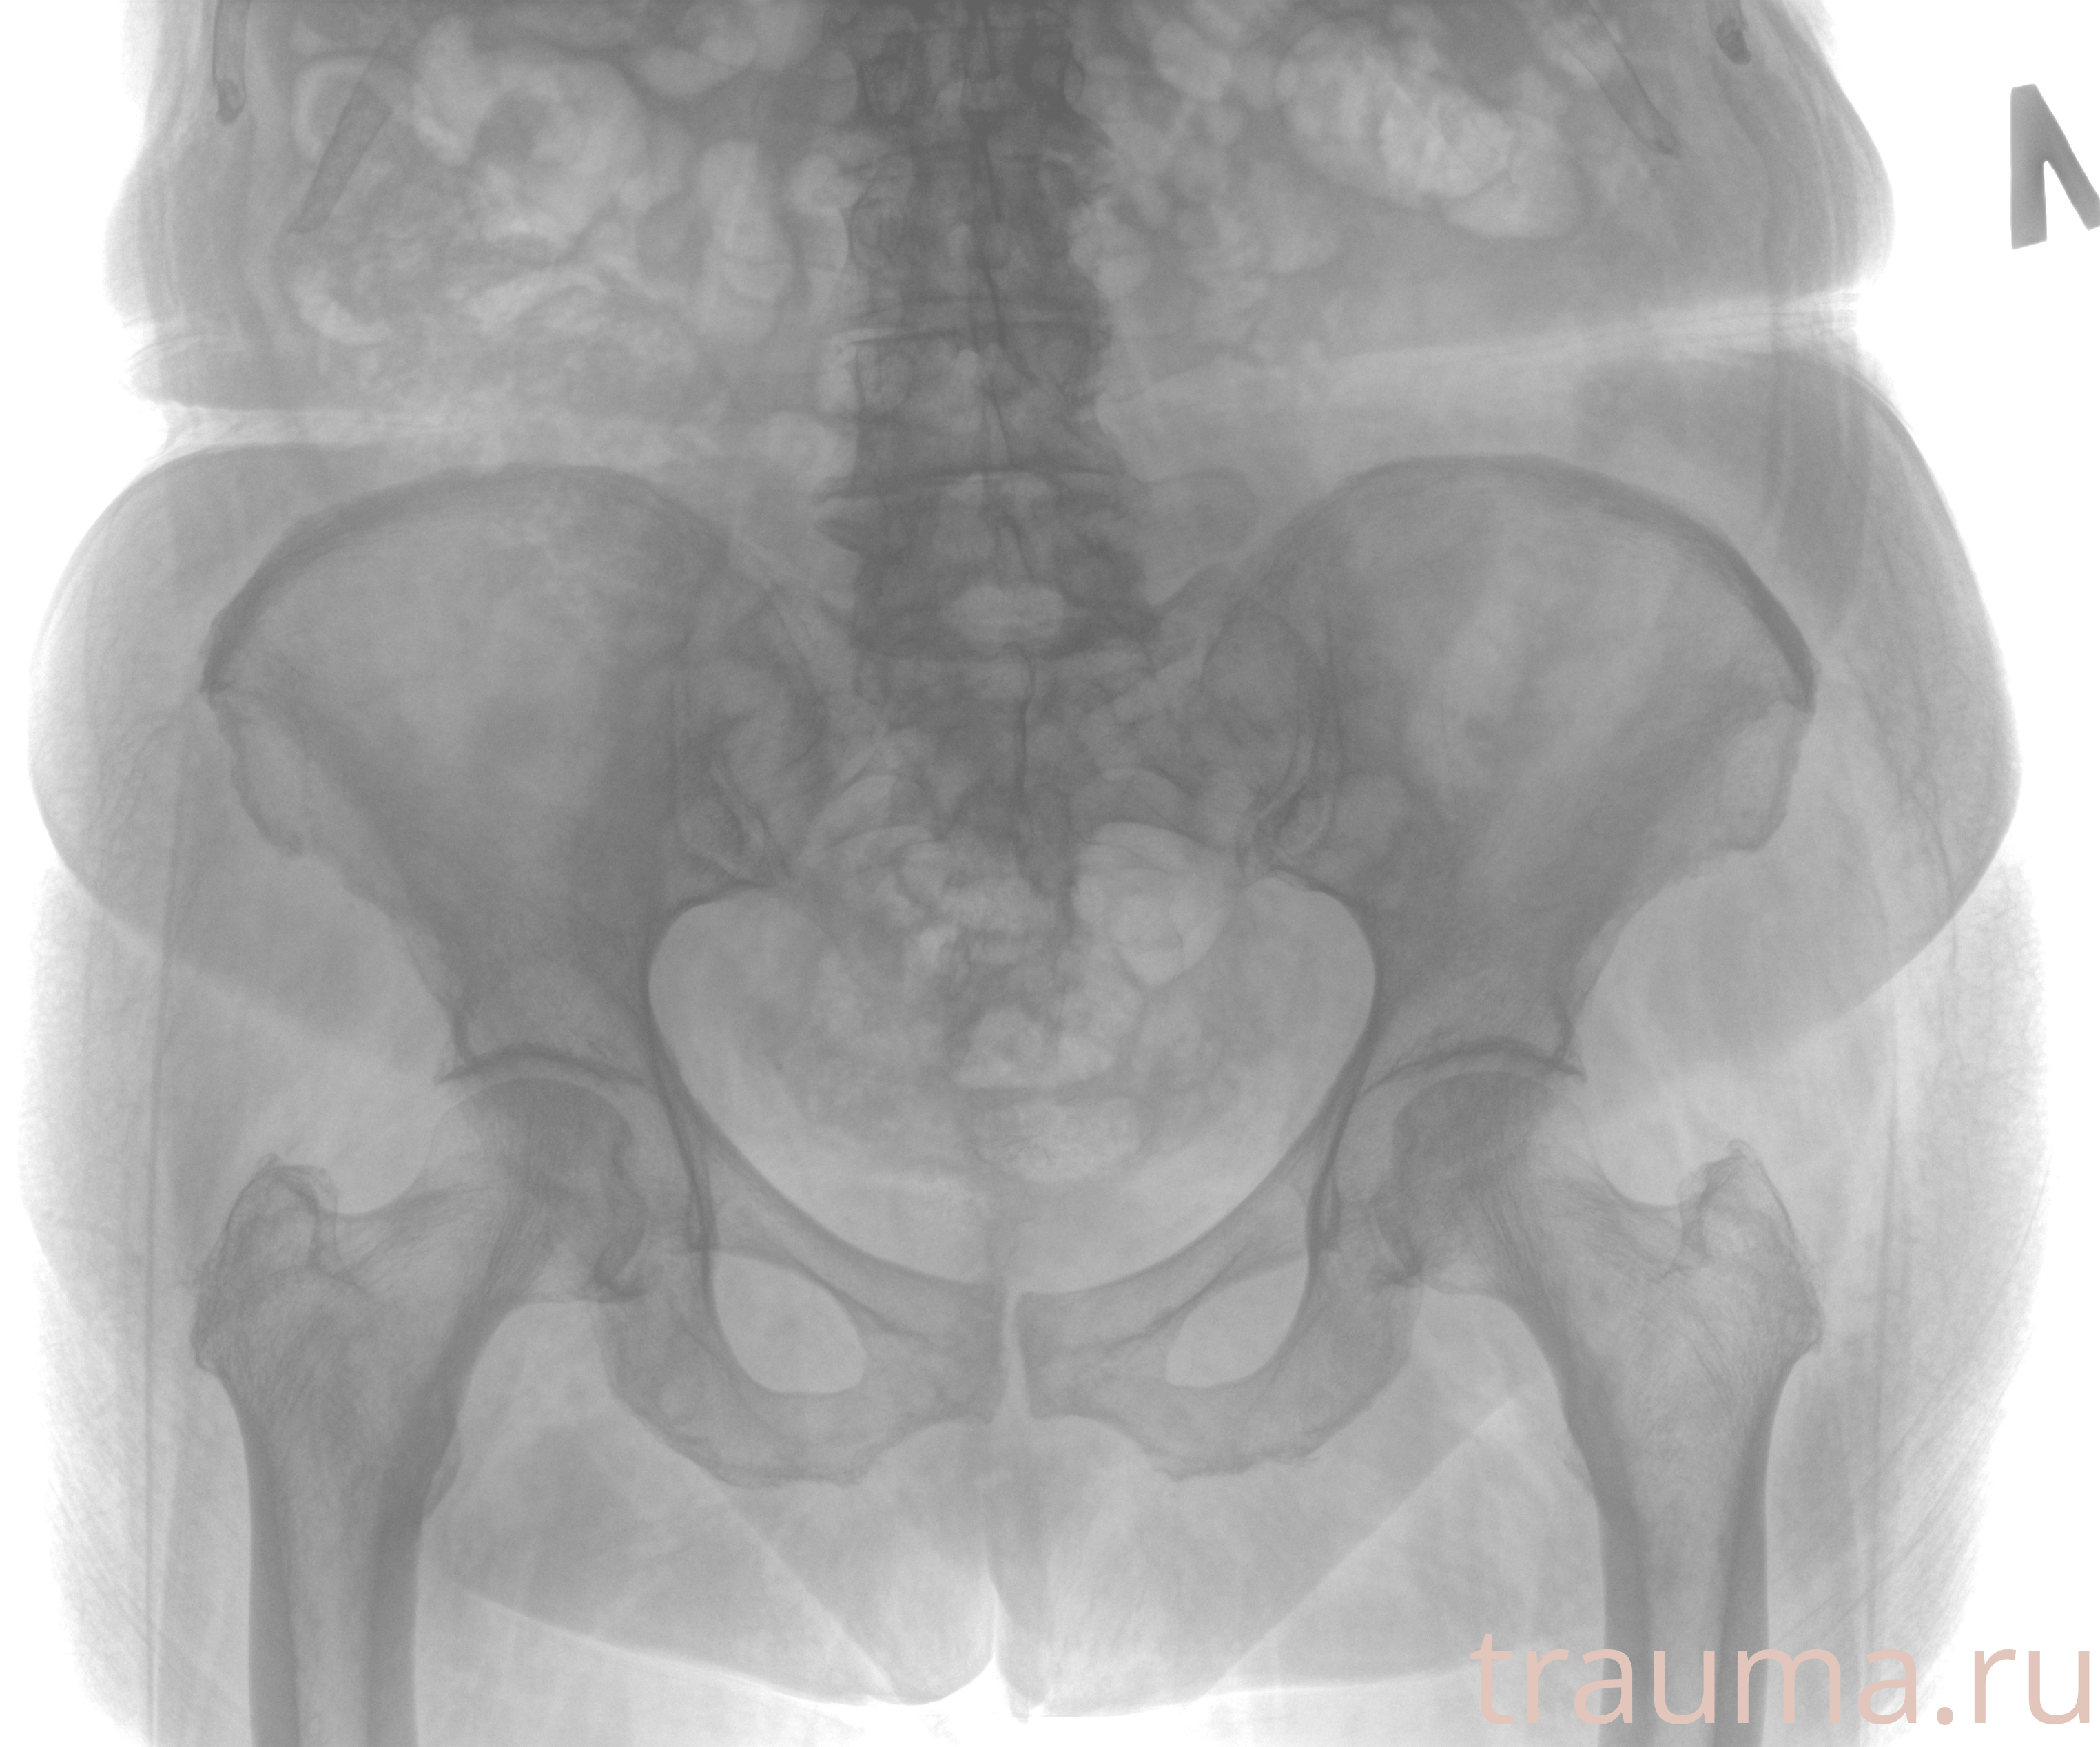

Рентгенограммы

Рентген на дому: по вашему адресу приезжает врач-рентгенолог, травматолог-ортопед с мобильным рентгеновским аппаратом, проводит диагностику травмы или заболевания, делает необходимые рентгенограммы, дает рекомендации по дальнейшему лечению. Получить качественные снимки в домашних условиях возможно благодаря уникальной методике, разработанной МосРентген Центром для института  Склифосовского